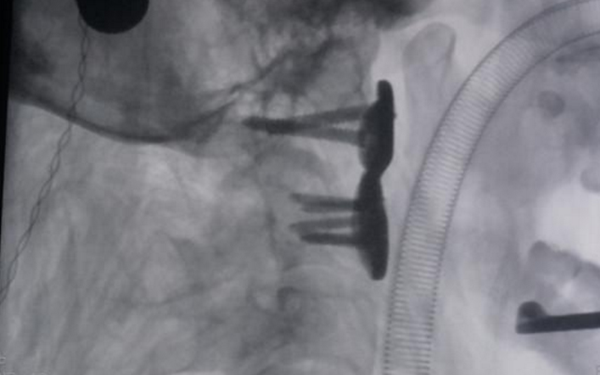

西安交通大學(xué)5月25日發(fā)布了兩項(xiàng)國(guó)際領(lǐng)先的最新科研成果,由交大二附院承擔(dān)的3D打印可動(dòng)人工頸椎假體項(xiàng)目,主要是利用3D打印技術(shù),為需要手術(shù)的嚴(yán)重頸椎病患者打印金屬鈦的頸椎,來(lái)更換病變的本體頸椎。目前,這個(gè)項(xiàng)目突破了國(guó)際上傳統(tǒng)的頸椎手術(shù)方法,具有完全自主知識(shí)產(chǎn)權(quán),已經(jīng)初步投入臨床應(yīng)用。

科研團(tuán)隊(duì)成員、西安交大二附院骨二科主治醫(yī)師蔡璇:“我們?cè)趥鹘y(tǒng)鈦籠鈦板植入融合這種手術(shù)方式上,發(fā)展出新型可動(dòng)人工頸椎。相較于傳統(tǒng)鈦籠融合手術(shù)而言,患者術(shù)后頸椎是可以保留活動(dòng)度的?!?/span>